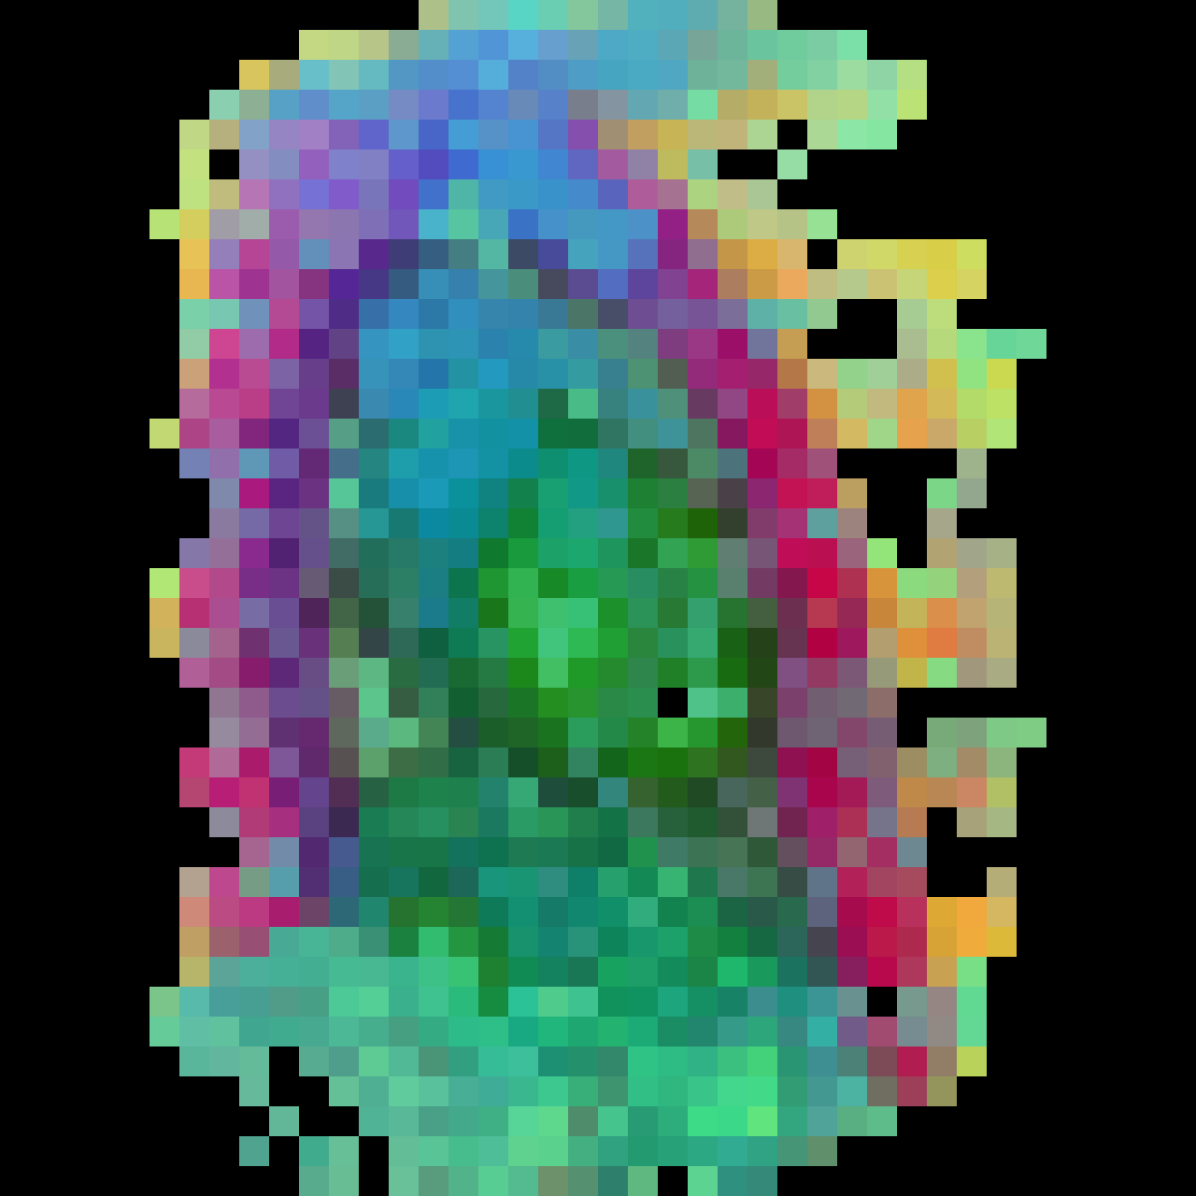

In this section we will show qualitative results of DINOv2 features using principal component analysis (PCA) performed on DINOv2 patch features on X-ray, CT, and MRI scans, following the method delineated in [8]. We will also provide organ segmentation results of linear compared U-Net decoders.

PCA visualization. Figure 2 shows the first three PCA components. The PCA is computed between patches of images that are in the same column, and the first 3 components are shown for X-ray, CT, and MRI scans. Thresholding is used on the first PCA component to remove the background. Just like in natural images [8], the colors of the three PCA components correspond well with the same parts of images in the same category. This is an easier task however, compared to natural images, because there is less variability between examinations on medical images compared to natural images.